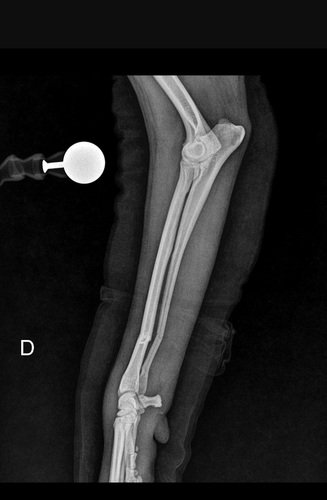

- Linhas de fraturas oblíquas e completas em diáfise distal de rádio e ulna direitos, com leve desvio do eixo ósseo.

- Aumento do volume de tecidos moles adjacentes ao foco de fraturas.

- Articulações umerorradioulnar e radiocárpica com relação preservada. Superfícies articulares lisas e regulares.

- Áreas de inserções tendíneas dentro da normalidade.

Impressão diagnóstica:

- Fraturas de rádio e ulna direitos, associado a edema dos tecidos adjacentes.

Encaminho paciente supracitado para realização de osteossíntese de rádio e una direita

Paciente adotado claudicando de membro torácico direito.

Com instabilidade de rádio e ulna. Radiografia confirmou fratura oblíqua curta de rádio direito